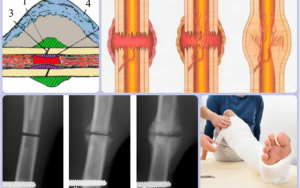

Перелом костной мозоли — это структура, которая образуется в процессе регенерации костной ткани. Он образуется в результате сложных восстановительных процессов. Чтобы не допустить серьезных осложнений, важно знать, как быстро образуется костная мозоль после перелома и опасно ли это для здоровья пациента. Что такое костная мозоль Причины образования костных мозолей Типы костных мозолей Этапы образования костной …